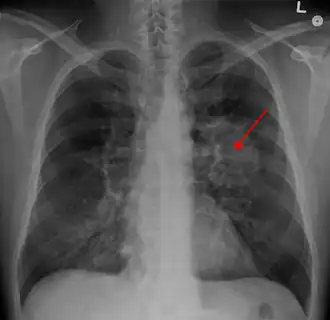

Tumoare pulmonară (marcată cu săgeată) vizibilă la radiografia toracică | |

Efectuarea unei radiografii toracice reprezintă unul dintre primii pași necesari pentru a investiga dacă o persoană prezintă simptome care pot sugera prezența cancerului pulmonar. Această radiografie poate arăta o masă evidentă, o extindere a mediastinului (sugerează răspândirea în nodulii limfatici), atelectazie (colabare), consolidare (pneumonie) sau revărsat pleural.[5] Imagistica prin computer tomograf este de obicei folosită pentru a oferi mai multe informații cu privire la tipul și gradul de extindere al bolii. Bronhoscopia sau biopsia ghidată CT este adesea folosită pentru a preleva mostre din tumoare pentru histopatologie.[13]

Cancerul pulmonar se prezintă, de cele mai multe ori, ca un nodul pulmonar solitar în cadrul unei radiografii toracice. Cu toate acestea, diagnosticul diferențial este extins. Multe alte boli pot să prezinte aceleași simptome, inclusiv tuberculoza, infecțiile fungice, cancerul metastatic sau pneumonia organizată. Printre cauzele mai puțin comune ale nodulului pulmonar solitar se numără hamartomul, chisturile bronhogenice, adenoamele, malformația arterio-venoasă, sechestrarea pulmonară, nodulii reumatoizi, granulomatoza Wegener sau limfomul.[45] Cancerul pulmonar poate fi, de asemenea, descoperit incidental, sub forma unui nodul pulmonar solitar la nivelul unei radiografii toracice sau tomografii computerizate realizate din alte motive.[46] Diagnosticul definitiv de cancer pulmonar are la bază examinarea histologică a țesutului suspectat în context clinic și radiologic.[4]